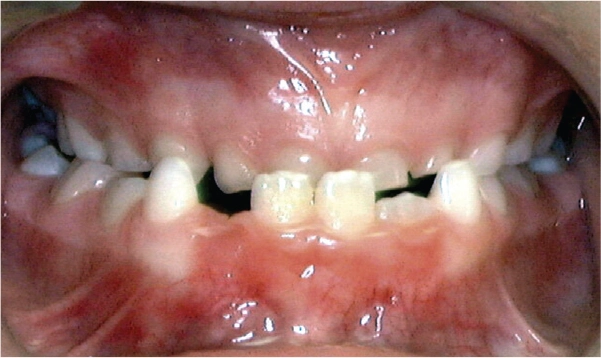

Open Bite